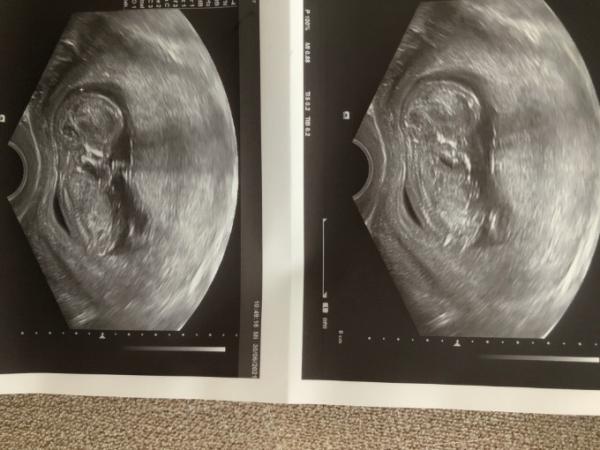

Hallo! :-) Ich darf mich nun auch offiziell vorstellen! Mein Name ist Julia, ich bin 24 Jahre alt & komme aus Niederösterreich. Das hier ist meine 1. SSW & ein absolutes Wunschkind … wobei wir nicht gedacht haben das es so schnell funktioniert Ich bin eher ein kleiner Angsthase & hab mich nie wirklich getraut es wen großartiges mitzuteilen… aber mit der jetzigen Woche gibt es mir ein besseres Gefühl! :-) Mein kleines Würmchen ist bereits 61,3 mm groß und hat heute am Daumen gelutscht :-D und meine FA hat mich auf 12+4 geschickt, obwohl ich erst bei 11+3 bin, das freut mich!! Ich freue mich schon auf die nächste Zeit & wünsche allen werden Mamis ebenfalls eine wunderschöne Kugelzeit!

Hallo Julia und herzlichen Glückwunsch! :) Wow, das ist ja ein wahnsinns Ultraschallbild!!! Super Qualität :) Wünsche dir eine schöne Schwangerschaft!

Herzlich willkommen und alles Gute zur Schwangerschaft. Echt zum beneiden dein Ultraschall Bild. Super Qualität und wunderschönes Foto. Alles Gute und liebe Grüße Melek

Hi Ist das ein süsses Bild, richtig goldig Als ich letztes mal Ultraschall hatte hat das Kleine nur den Hintern immer zu uns gedreht. Egal was die Ärztin auch versuchte bekamen wir nicht viel mehr zu sehen